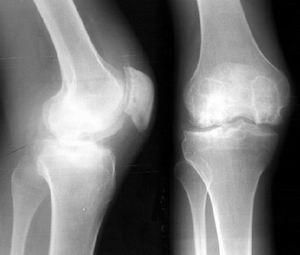

X線檢查

骨刺X線平片不僅為骨質增生的常規檢查方法,有的學者還認為骨質增生的X線檢查是追蹤病情變化的金標準。

骨刺的X線片可分為五級:

0級:無改變;

1級:輕微骨贅;

2級:明顯骨贅,關節間隙正常;

3級:骨贅外關節間隙中度狹窄;

4級:骨贅外關節間隙嚴重狹窄,伴軟骨下骨硬化。

拍膝關節片時,病人應取站立位拍前後位和側位片,髖關節和手關節可只拍前後位片。在早期階段,X線片大多正常,中晚期可見關節間隙不對稱性狹窄、關節面下骨硬化和變形、關節邊緣骨贅形成,關節面下囊腫和關節腔游離液體等。

骨質增生的x線特點為:關節面硬化變形;關節鼠;關節邊緣骨贅;關節間隙狹窄,如在膝關節,可小於3毫米;軟骨下囊性變,其邊緣分界清楚;骨變形或關節半脫位。